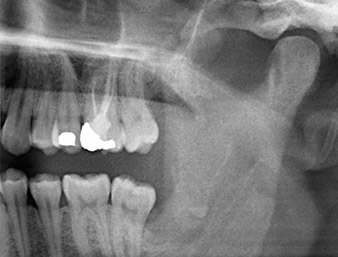

A 26-year old patient complained of constant pain and paraesthesia after surgical removal of a retained wisdom tooth. Panoramic radiographs confirmed a root remnant located in close proximity to the inferior alveolar nerve.

The root remnant in the region of tooth 38 (LL8) was already displaying close proximity to the inferior alveolar nerve on the OPG. The root had fractured during the osteotomy but had not been removed by the primary treatment provider due to intraoperative pain. To ensure as little trauma as possible to the tissue, the new osteotomy was to be carried out using a piezo surgical system. The patient had an unremarkable medical history and was a non-smoker.